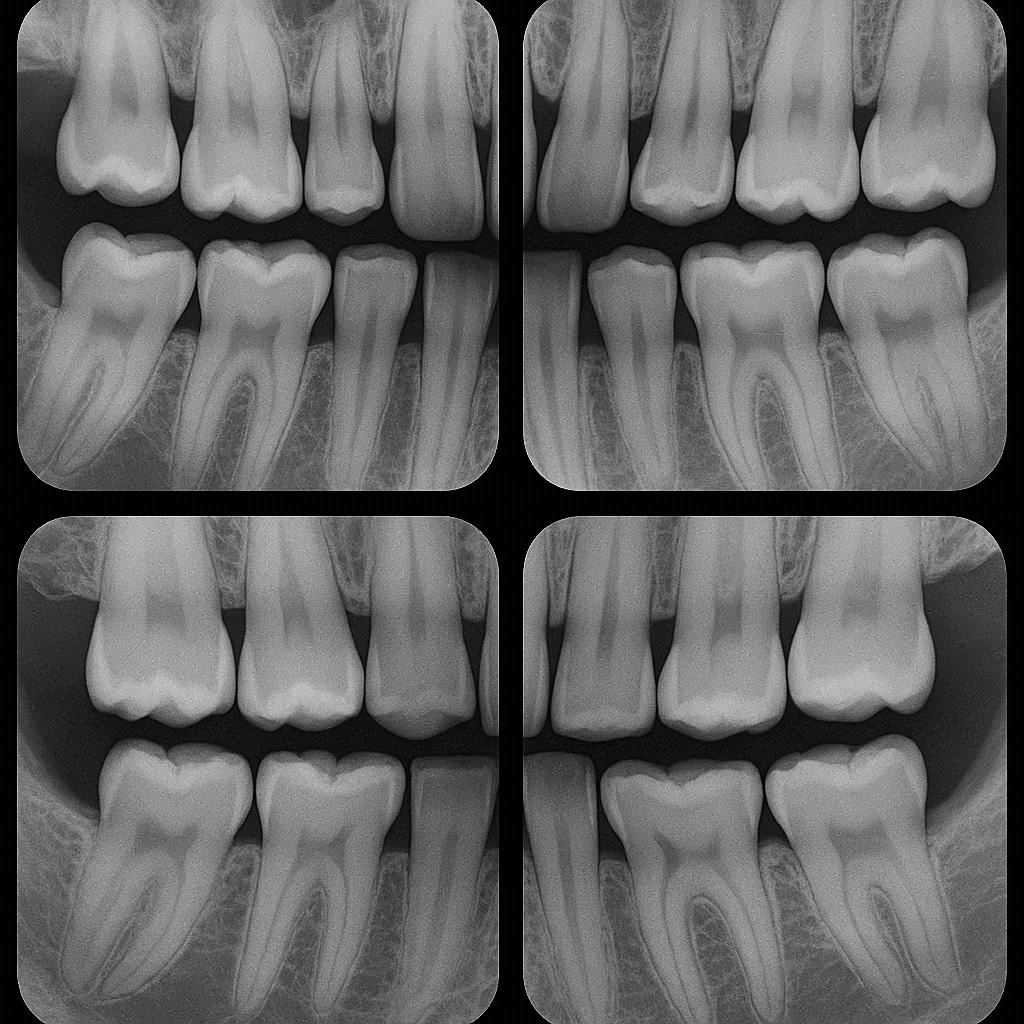

Bitewings are a type of dental X-ray that shows the crowns of your upper and lower teeth in one single view. They are called “bitewings” because you bite down on a small tab or wing-shaped sensor holder.

Traditional bitewings are horizontal. That means the long side of the image runs left to right. These are perfect for looking at cavities between teeth and checking the height of bone crests in patients with healthy gum levels.

Vertical bitewings, however, are rotated 90 degrees. The long side of the image runs up and down.

Because vertical bitewings show more bone. They allow you to see the crestal bone level and a deeper portion of the root. This makes them especially useful for patients with moderate to advanced periodontal disease.

So when you take four vertical bitewings, you are typically covering the premolar and molar regions on both the left and right sides, using the taller orientation to capture more vertical information.